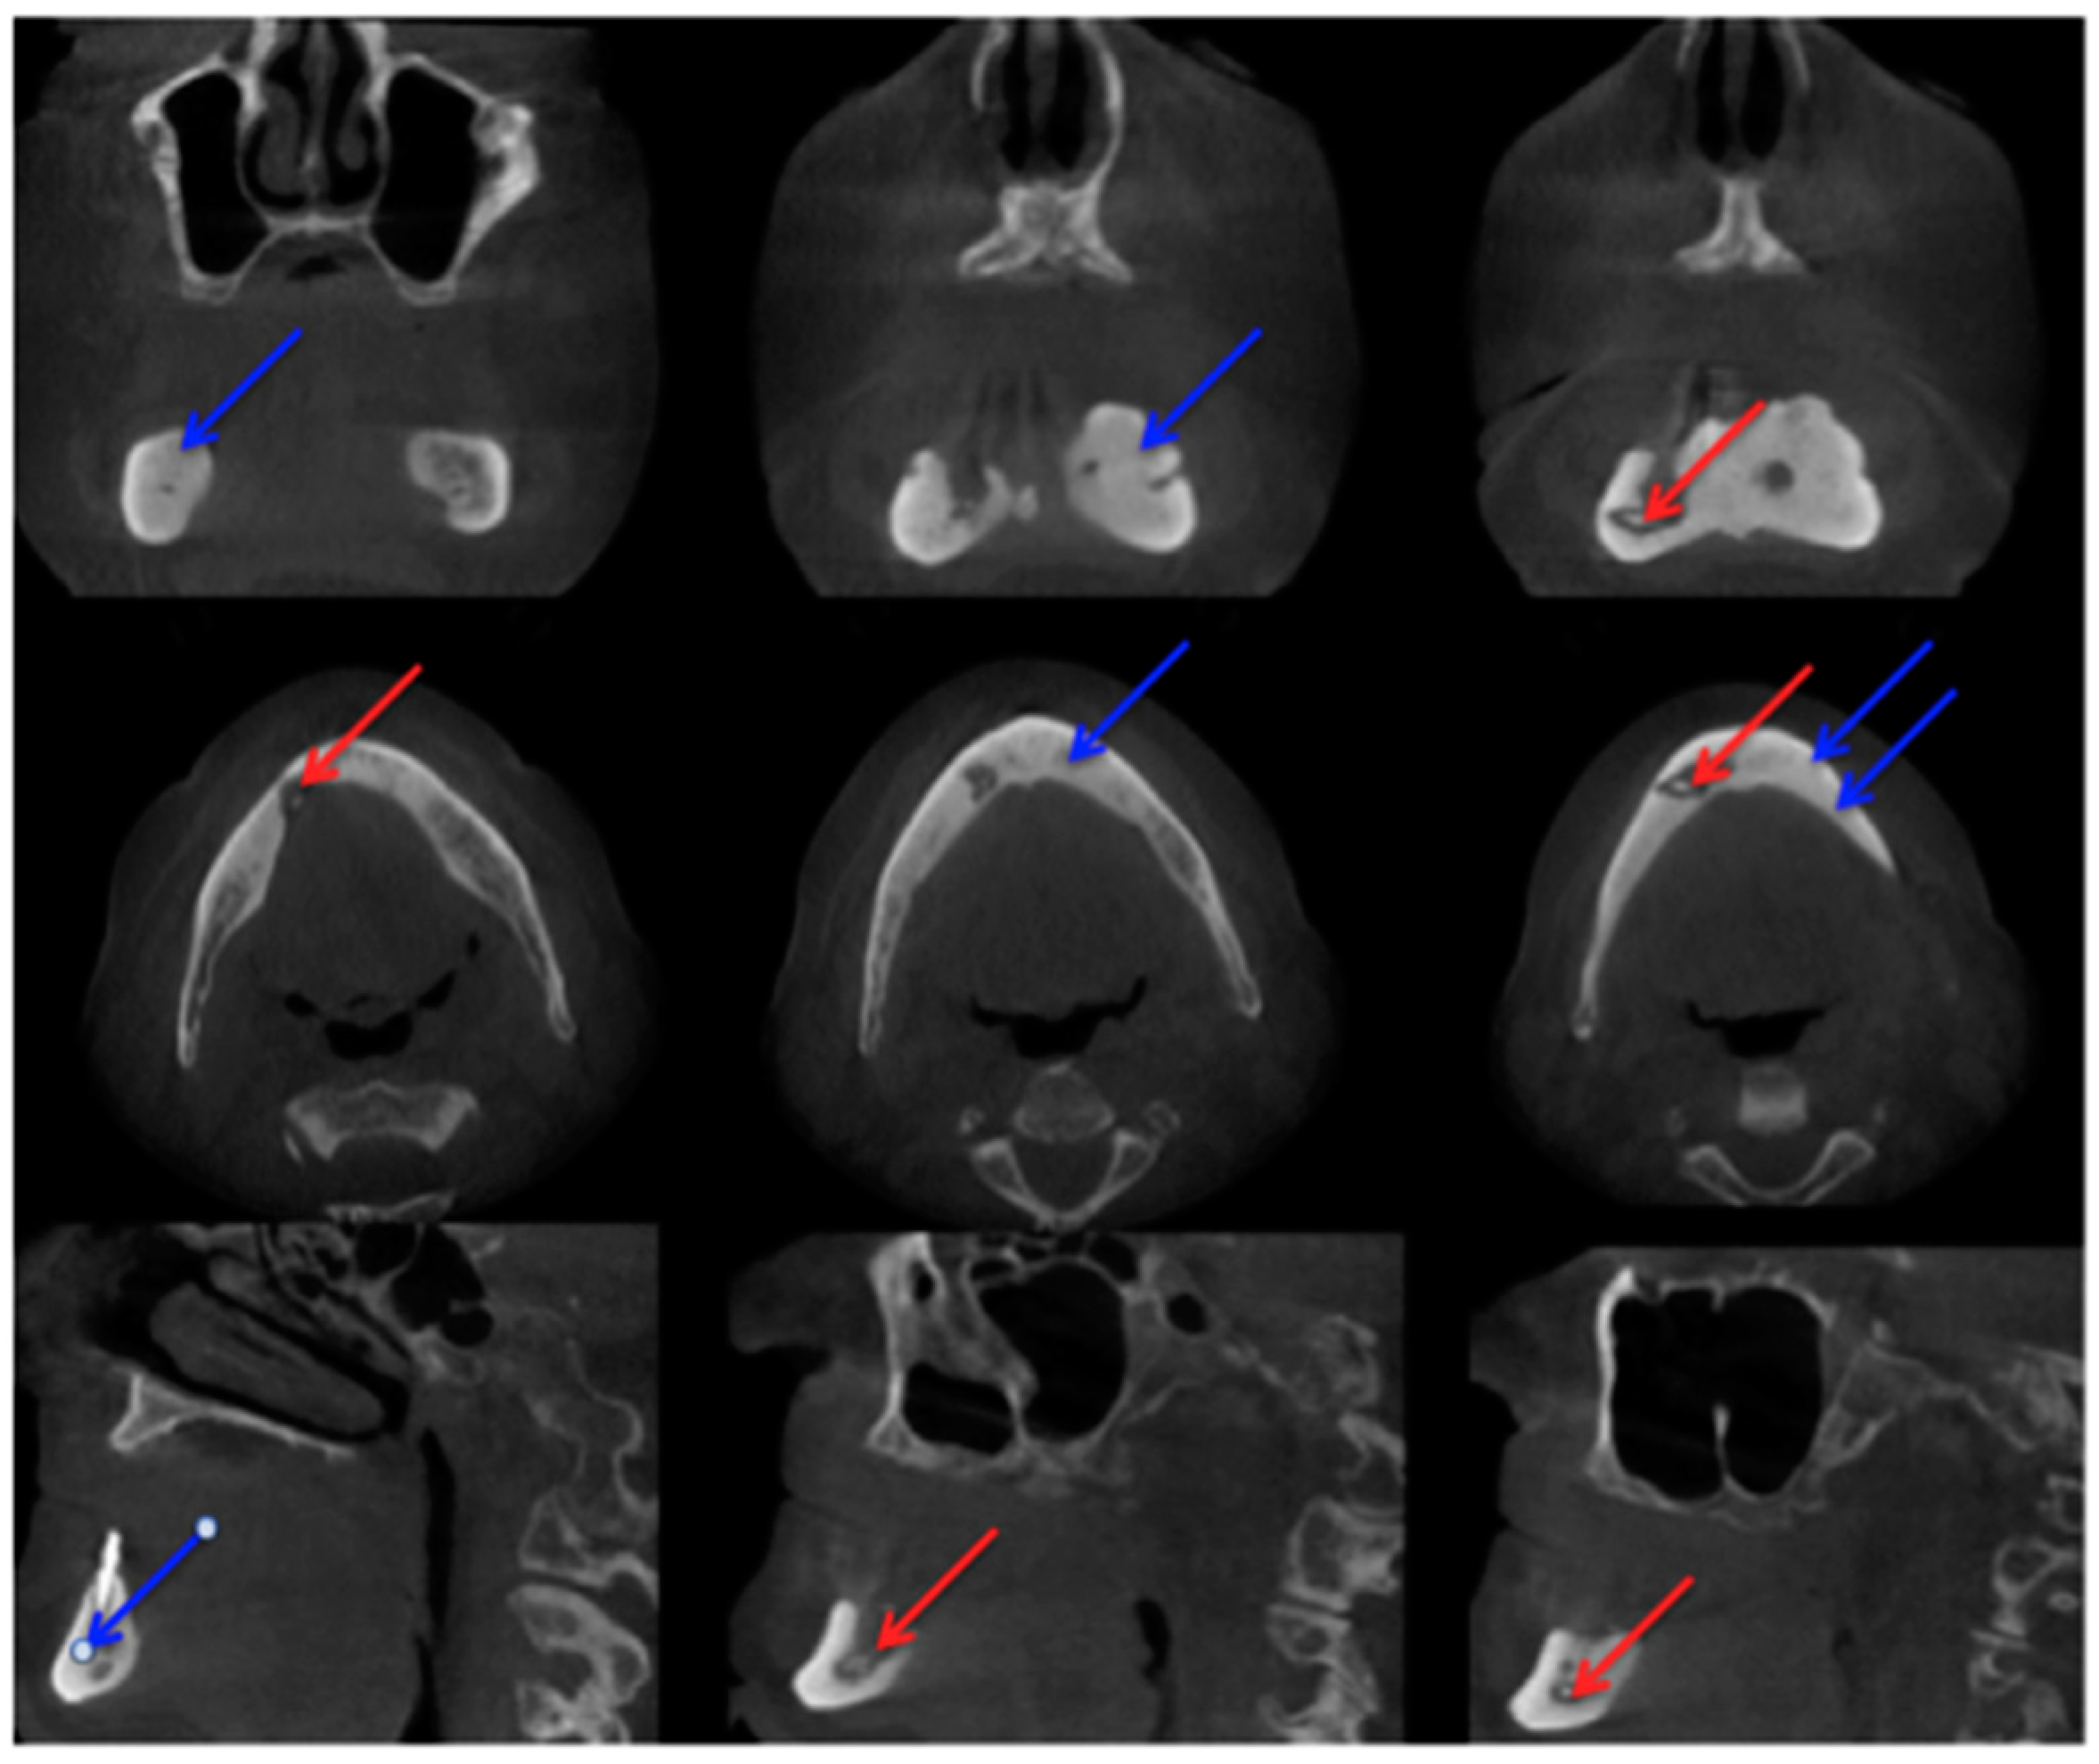

In comparison with MRI and CT, there are fewer papers about imaging of MRONJ with CBCT [23]. Before Torres et al. investigated mandibular inferior cortical bone thickness [16], they studied cortical bone dimensional changes in MRONJ patients using CBCT data sets. By assessing the data sets (12 patients/66 test persons) using three different techniques, they could show that “the cortical bone measurements were significantly higher in cases than controls for all 3 techniques” [24]. As stated in Yalcin and Gungormu’s review, typical findings in CBCT and CT are “pathologic fractures, narrowing of the marrow space and involvement of the inferior alveolar canal” [23]. Figure 4 shows a patient with narrowing of the marrow space and sequestra from our clinical database.

Figure 4.

Cone-beam computed tomography (Carestream CS 9300) Patient: 77 years old, metastatic prostate cancer, ibandronic acid and later another antiresorptive drug: denosumab. For panoramic radiograph see Figure 2. 1st row: coronary view; 2nd row: axial view; and 3rd row: sagittal view. Red arrows: sequester; blue arrows: sclerotic region. AAMOS staging: stage 2.